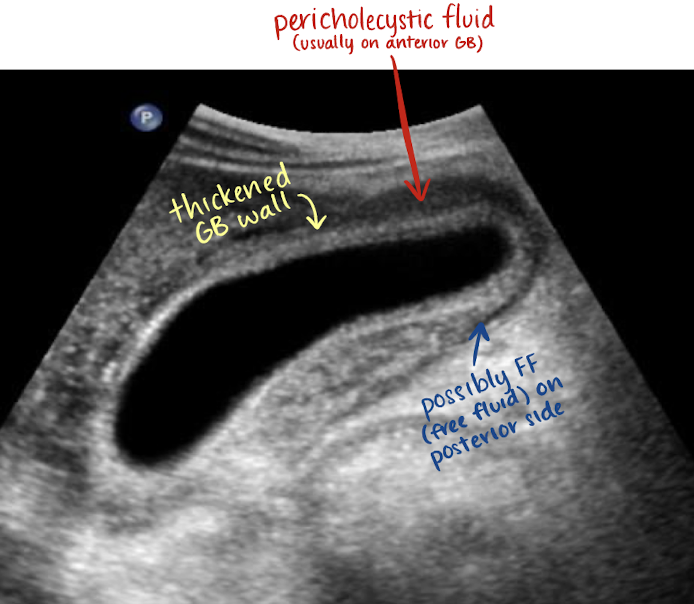

SONO: acute cholecystitis

+ Murphy’s sign

irregular wall > 3 mm

gallstones usually present

wall edema

hyperemia due to inflammation

pericholecystic fluid may be present

??

acute cholecystitis

thickened GB wall

pericholecystic fluid in anterior GB

?FF in posterior GB